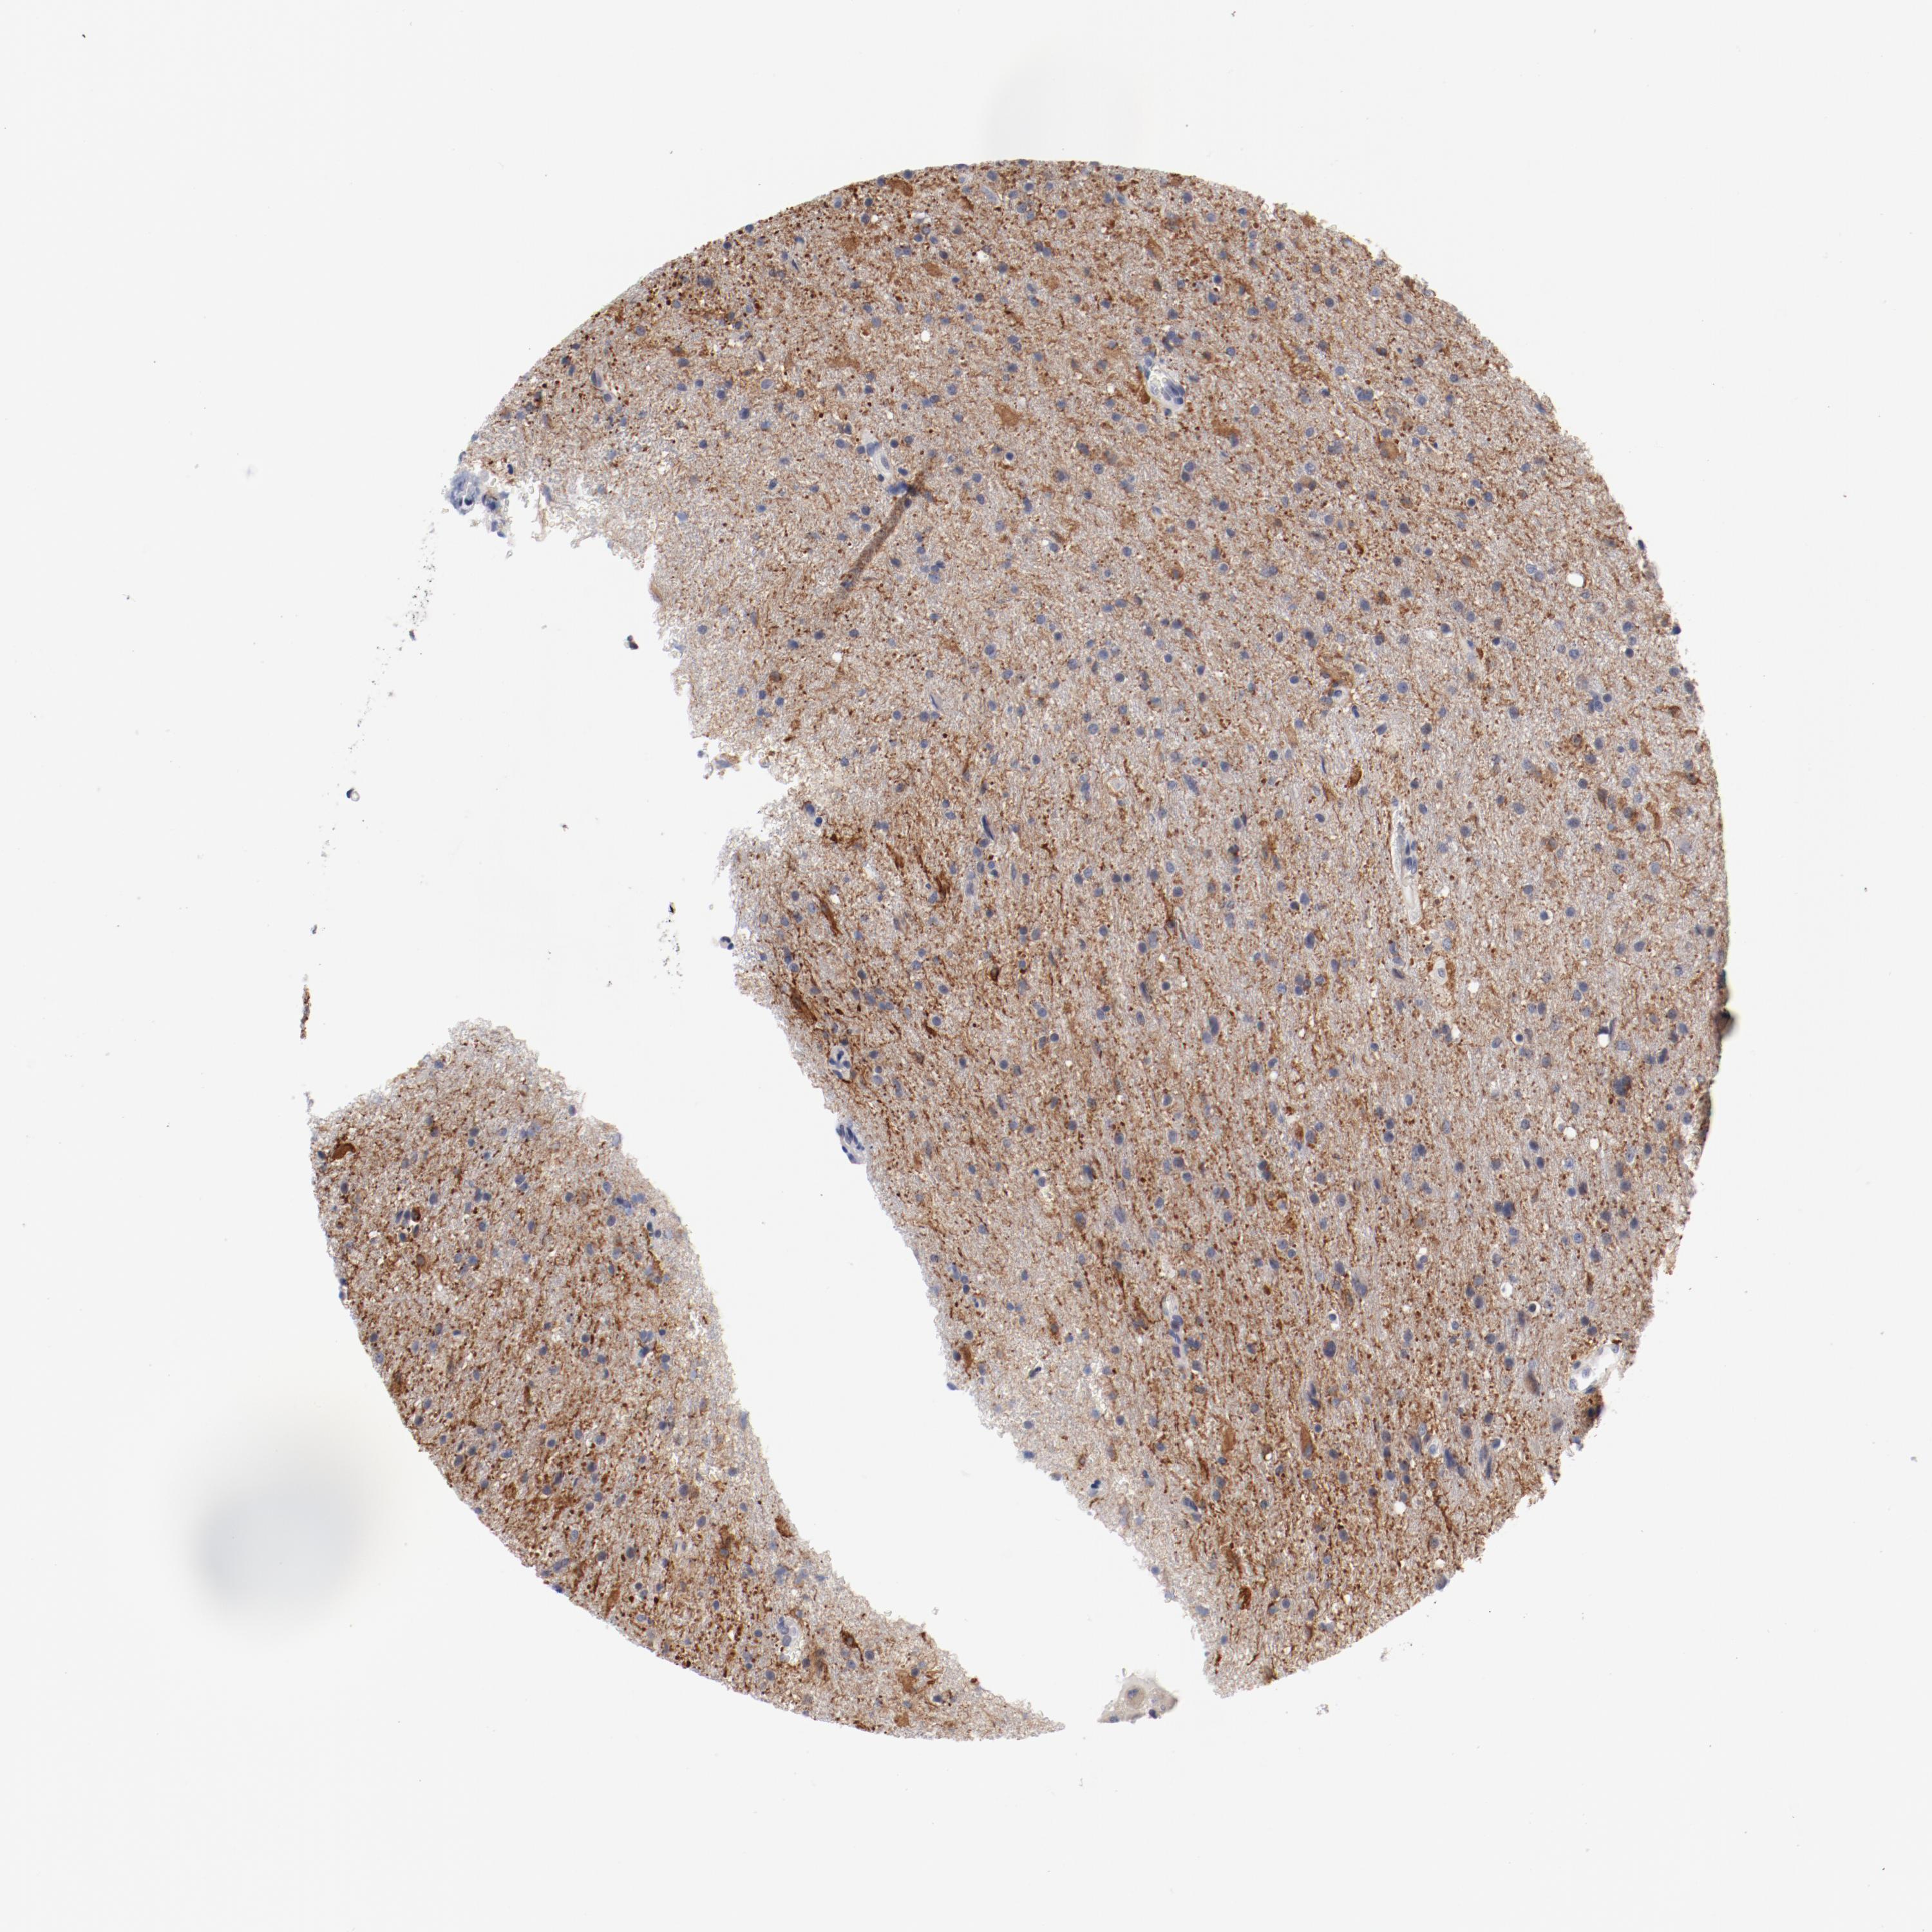

GLIOMA - Protein expressioni

A mouse-over function shows sample information and annotation data. Click on an image to view it in a full screen mode. Samples can be filtered based on level of antibody staining by selecting one or several of the following categories: high, medium, low and not detected. The assay and annotation is described here.

Note that samples used for immunohistochemistry by the Human Protein Atlas do not correspond to samples in the TCGA dataset.

Antibody stainingi

Antibody staining in the annotated cell types in the current human tissue is reported as not detected, low, medium, or high, based on conventional immunohistochemistry profiling in selected tissues. This score is based on the combination of the staining intensity and fraction of stained cells.

Each image is clickable and will lead to virtual microscopy that enables deeper exploration of all samples and also displays staining intensity scores, fraction scores and subcellular localization as well as patient and tissue information for each sample.

Antibody HPA003514

Staining

High

Medium

Low

Not detected

Intensity

Strong

Moderate

Weak

Negative

Quantity

>75%

75%-25%

<25%

None

Location

Nuclear

Cytoplasmic/membranous

Cytoplasmic/membranous,nuclear

Glioma, malignant, High grade

Glioma, malignant, Low grade

Glioma, malignant, NOS